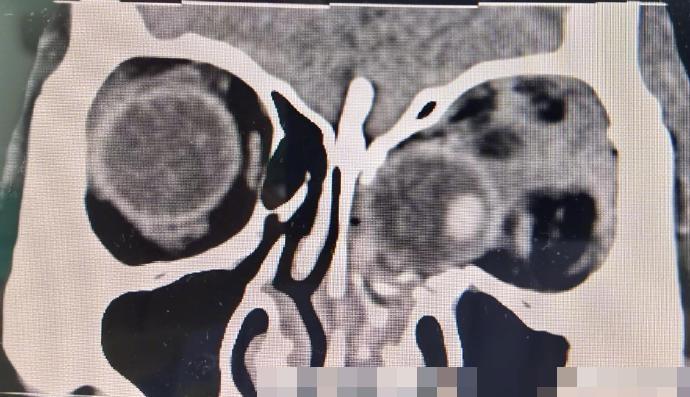

綜合《貴州日報》、《北京日報》等內地媒體報道,貴州醫科大學附屬醫院創傷科近日接獲一宗特殊病例,病者為一名50歲女子,因一腳踩空不慎從3樓墜落,導致全身多處疼痛及左眼視力喪失,被送往該院救治。經檢查後,發現病者的左眼球脫位,並嵌頓於鼻腔內,情況十分危急。經過近4個小時的緊張手術,眼球成功復位到左眼眶內,並修得了眼眶爆裂性骨折。由於手術採取了微創手術切口,病者的外觀並未留下手術疤痕。術後第一天,病者的左眼便恢復光感,這意味著她的左眼視功能得以保留,為今後的康復創造了條件。